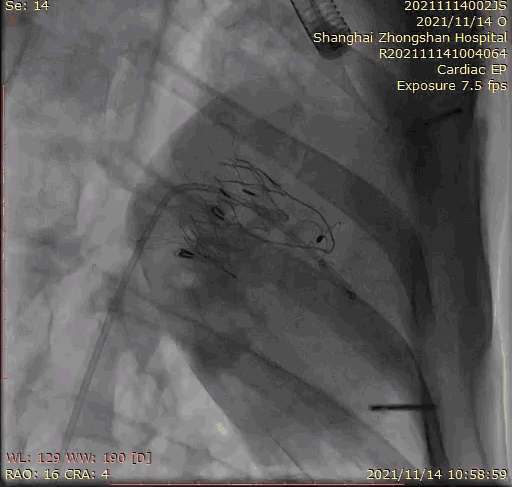

2021年11月14日星期日,復(fù)旦大學(xué)附屬中山醫(yī)院(以下簡(jiǎn)稱中山醫(yī)院)葛均波院士團(tuán)隊(duì)成功應(yīng)用經(jīng)血管介入三尖瓣置換產(chǎn)品Lux-Valve Plus完成臨床前研究,并獲得圓滿成功!此次研究的成功預(yù)示經(jīng)血管三尖瓣產(chǎn)品Lux-Valve Plus已完成臨床前準(zhǔn)備,即將開啟后期的正式臨床研究!

上海中山醫(yī)院葛均波院士、錢菊英院長(zhǎng)、周達(dá)新教授、潘文志教授、潘翠珍教授、李偉教授共同完成此次臨床前研究。術(shù)后葛均波院士對(duì)Lux-Valve Plus的器械操作性能給予了高度評(píng)價(jià),DSA和超聲影像也顯示出在本次研究中Lux-Valve Plus的安全性和有效性俱佳。

本次臨床前研究經(jīng)右側(cè)頸靜脈置入LuX-Valve Plus輸送系統(tǒng)可調(diào)彎鞘管,在DSA及超聲引導(dǎo)下將人工三尖瓣瓣膜植入到原有三尖瓣位置,利用獨(dú)特的錨定技術(shù)將人工瓣膜支架可靠固定在預(yù)定的位置。